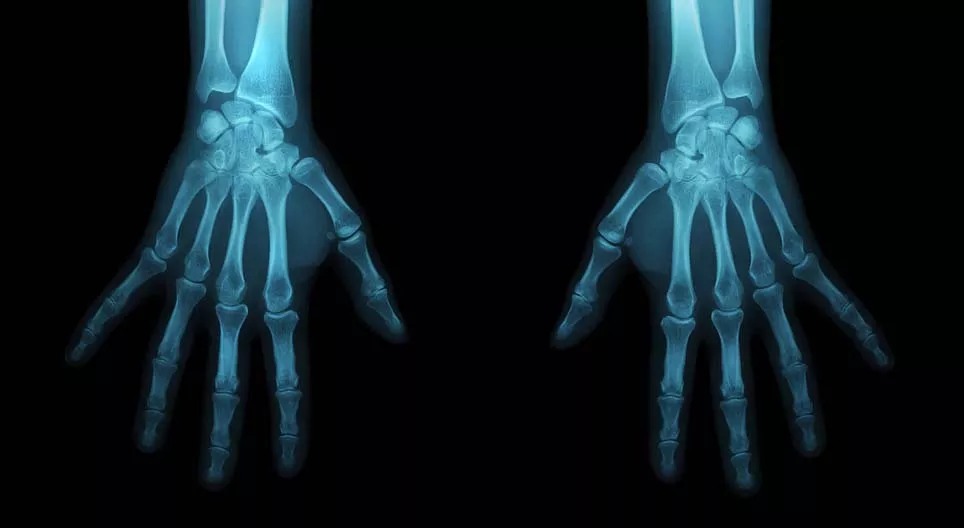

Ismerkedjünk meg a csontok típusaival és az antropológusok munkájával!